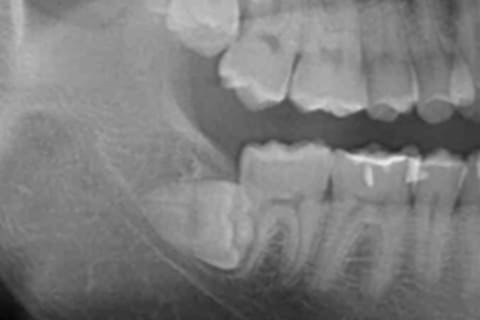

Step6

レントゲン撮影やCT撮影

詳しいお口の状態などを調べるため、レントゲン・CTスキャンを撮影させていただきます。